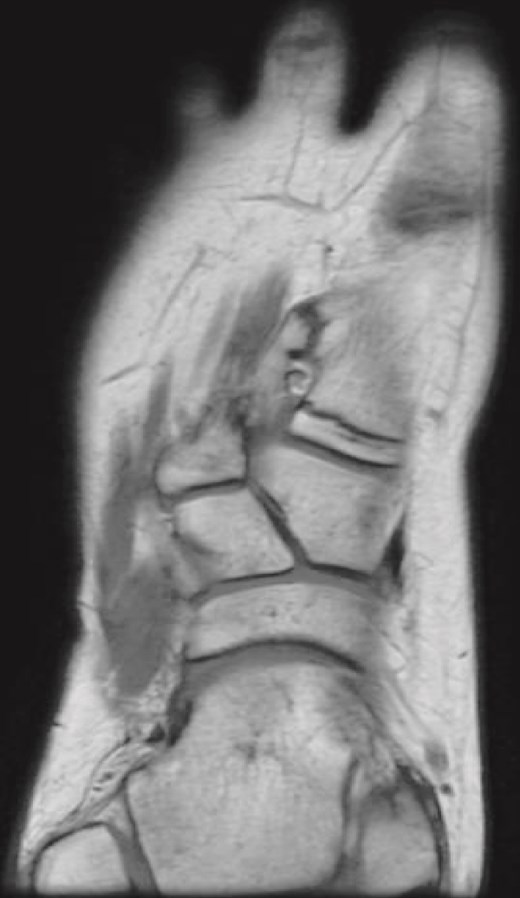

Plain radiographs revealed a bony mass extending from the medial cuneiform to the first metatarsal, with the first and second intermetatarsal space widening (Fig. 1). Magnetic resonance imaging (MRI) was performed to better characterize the mass (Fig. 2). Musculoskeletal radiologists reported the presence of an abnormal rudimentary bone that was interposed between the first and second metatarsal bones, with pseudo-articulation and ankylosis with the lateral aspect of the mid-metatarsal shaft of the hallux, causing widening and deformity, suggesting a supernumerary rudimentary metatarsal bone. An osteochondroma was also considered in the differential diagnosis, but the cartilage cap was not clearly visible. As daily activities were significantly affected, the patient’s guardian preferred surgical excision over more conservative measures, which had previously been unsuccessful.

Coronal T1-weighted MRI of the right foot showing a rudimentary bone interposed between the first and second metatarsals with pseudo-articulation and ankylosis with the midshaft of the first metatarsal.